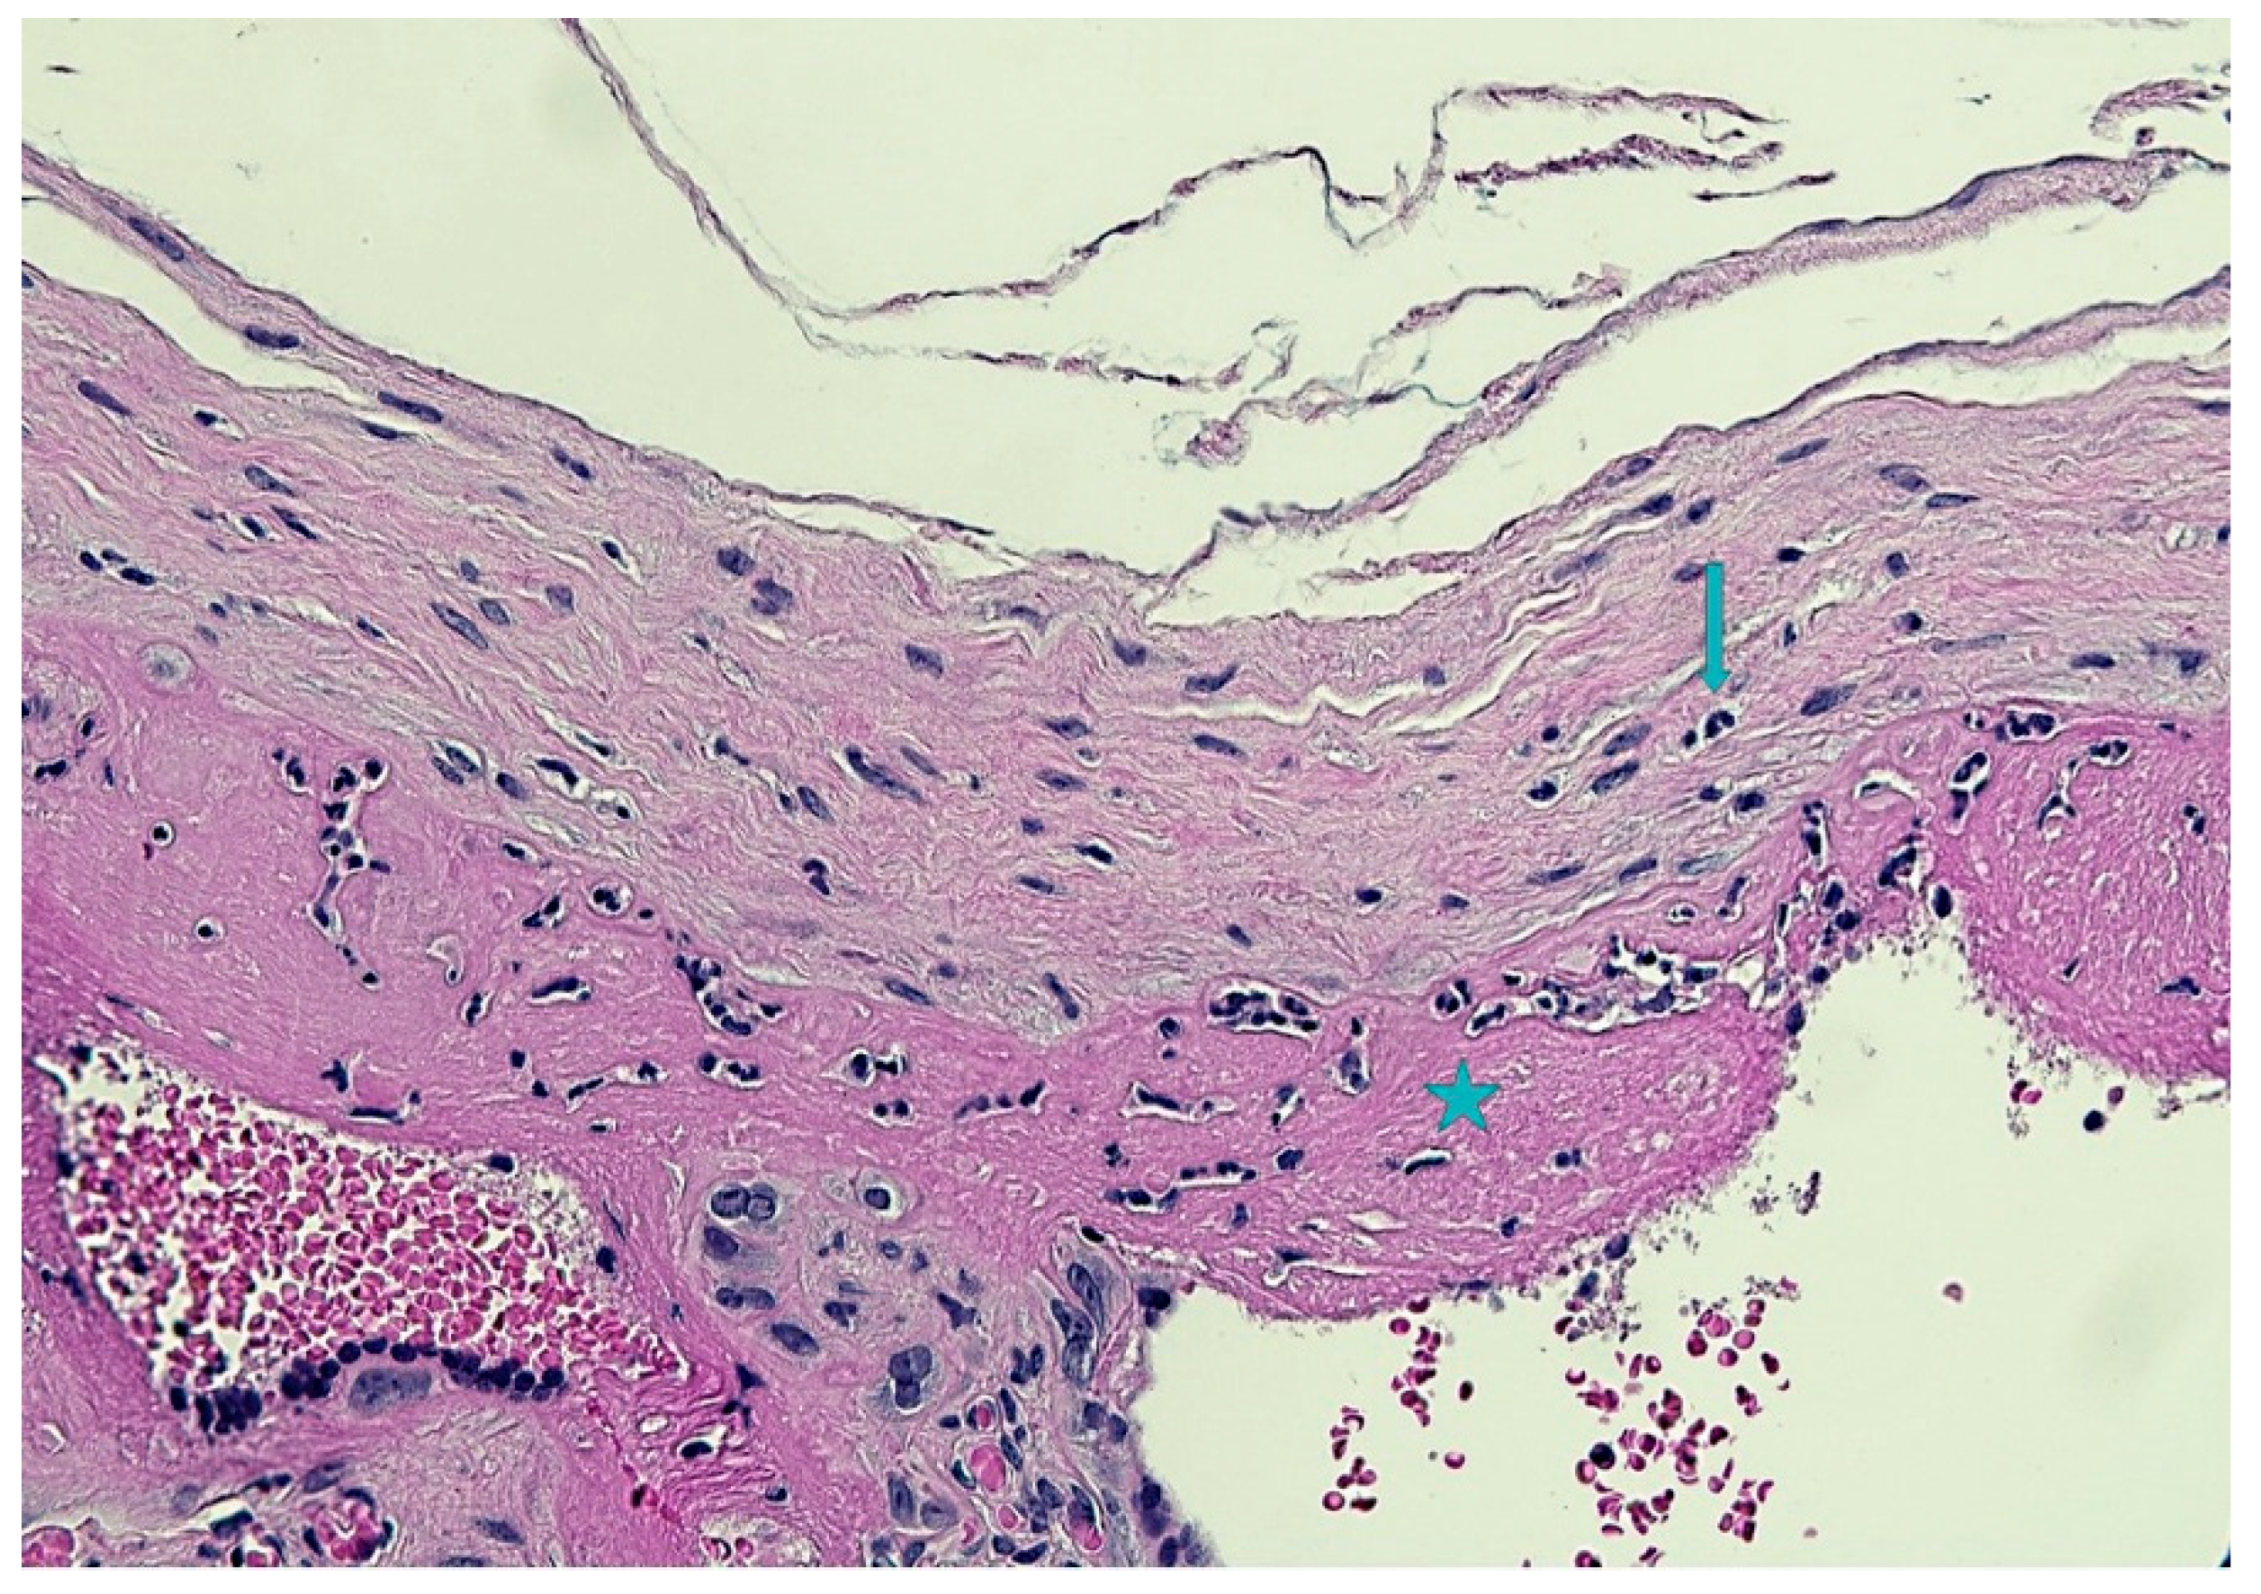

2. The Case